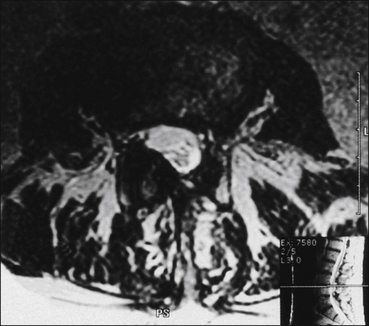

A variation of the spinal stenosis problem occurs with compression of an isolated root in a spondylotic foramen. Patients have complaints similar to those of acute disc herniation, but the time course is protracted and the onset has usually been gradual. Patients complain of sciatica or femoral pain in the accepted distribution of a single root. Sometimes the root involvement is bilateral, and occasionally more than one root on one side is affected. However, the syndrome is not of claudication but of ongoing root compression; that is, the pain tends to be constant, although it is often exacerbated by activity, being upright, and axial loading. The associated reflex, motor, and sensory changes relate to the individual root. A positive straight-leg rising test is unusual and is different from the tension sign of acute disc herniation. The diagnosis is made by MRI (Fig. 71-4) and CT, which visualize the neural foramina and compression of the nerve root.

Figure 71-4 Axial magnetic resonance image demonstrating unilateral facet hypertrophy with encroachment on the spinal canal and foraminal stenosis.

The change is at L3–4 and the patient’s symptoms were right-sided anterior thigh pain.